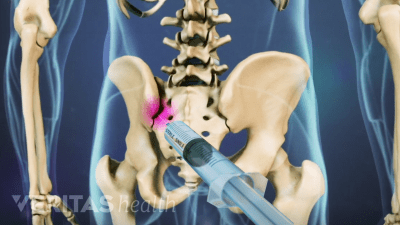

Discover the best radiographic tests for diagnosing SI joint dysfunction and ruling out serious medical conditions.